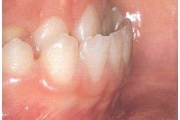

Normaalse jäävhammaskonna pilt küljelt ja eest vaadatuna.